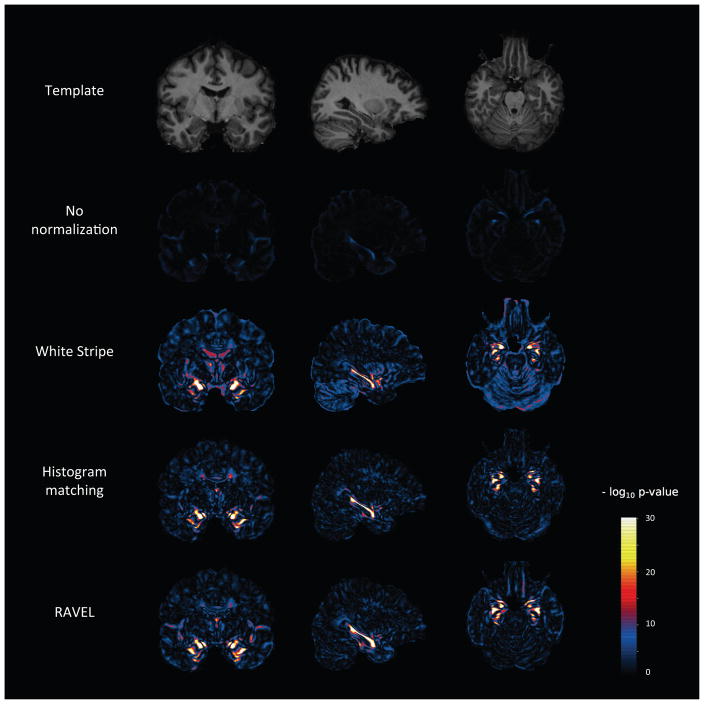

Figure A.3. Voxel-level p-value maps from AD vs. healthy patient differential analysis.

At each voxel, we computed a t-statistic for testing a difference in intensities between AD and healthy patients. For each normalization method, we report the negative log p-values from the t-test. We include at the top of the figure the template for anatomical reference.